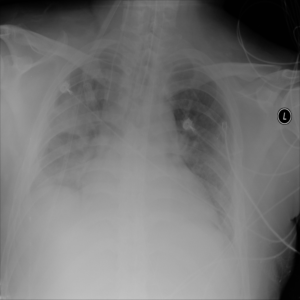

Figure 6: Examples of normal (left) and anomaly (right) images of H&E-stained lymph node of Camelyon16 challenge [3] (top) and chest X-rays of NIH dataset [4] (bottom). We also showed the predicted anomaly score by the proposed method. The higher the score, the more likely to be an anomaly. Notice how the proposed method spots even the borderline cases.

We illustrate the predictions of our model in Figure 6.

Anomaly Detection on Chest X-Rays

Chest X-ray is one of the most common examinations for diagnosing various lung diseases. We considered the task of the recognition of fourteen findings, such as Atelectasis or Cardiomegaly, on the chest X-rays in the NIH dataset (ChestX-ray14 dataset) [4] (Figure 2). Searching abnormalities on a chest x-ray is challenging even for an experienced radiologist since abnormality may occupy only a small region of lungs, or be almost invisible. The dataset consists of 112,120 frontal-view images of 30,805 unique patients: 86523 for training, 25595 for evaluation. We split the dataset into two sub-datasets having only posteroanterior (PA) or anteroposterior (AP) projections, because organs on them look differently. We tried different preprocessing during the hyperparameter search: rescaling to 256x256, 128x128, and 64x64 and histogram equalization, central crop (3/4 of the image size) to delete “noisy” borders. We considered images without any disease marker as “normal” and used them for training. Abnormal images for hyperparameter searching comprised of the training images of the most frequent disease (‘Infiltration’) out of fourteen possibilities. We also evaluated model on subset containing “clearer” normal/abnormal cases (provided by  [22]). This subset consists of 4261 normal images for training, 849 normal and 857 abnormal images for validation, and 677 normal and 677 abnormal images for testing.